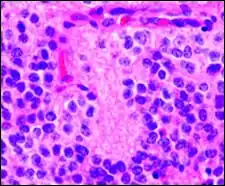

Perivascular pseudorosette

A perivascular pseudorosette consists of a spoke-wheel arrangement of cells with tapered cellular processes radiates around a wall of a centrally placed vessel. The modifier “pseudo” differentiates this pattern from the Homer Wright and Flexner-Wintersteiner rosettes, perhaps because the central structure is not actually formed by the tumor itself, but instead represents a native, non-neoplastic element. Also, some early investigators argued about the definition of a central lumen, choosing “pseudo” to indicate that the hub was not a true lumen but contained structures. Nevertheless, this pattern remains extremely diagnostically useful and the modifier unnecessarily leads to confusion. Perivascular pseudorosettes are encountered in most ependymomas regardless of grade or variant. As such, they are significantly more sensitive for the diagnosis of ependymomas than true ependymal rosettes. Unfortunately, perivascular pseudorosettes are also less specific in that they are also encountered in medulloblastomas, PNETs, central neurocytomas, and less often in glioblastomas, and a rare pediatric tumor, monomorphous pilomyxoid astrocytomas.[2]

Micrograph of perivascular pseudorosettes

Micrograph of perivascular pseudorosettes Structure of a perivascular pseudorosette

Structure of a perivascular pseudorosette